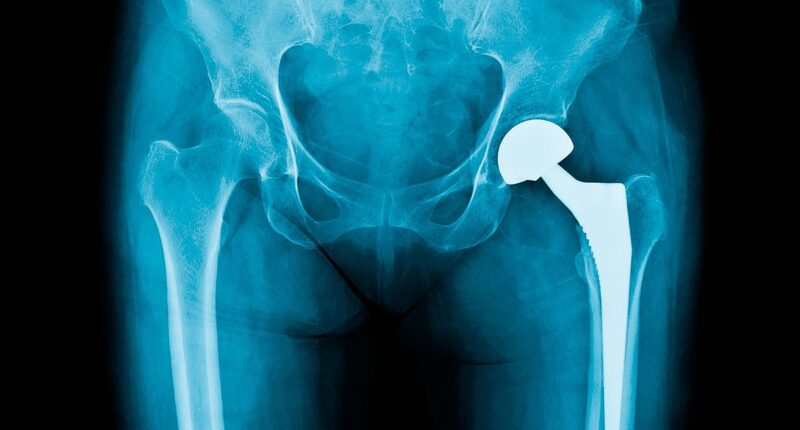

Bone cement, which is used to lock the replacement in place and get patients back to normal life quicker, is used in the majority of the 250,000 procedures carried out each year.

The crucial ingredient is thought to be used in more than 80 per cent of knee replacements and almost 60 per cent of hip replacements – which equates to around 15,000 operations every month.